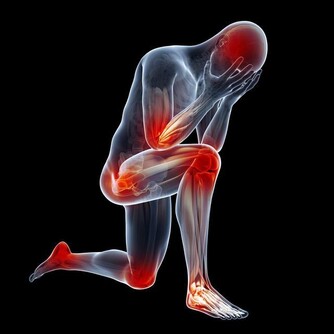

人的腳底匯集了無數的穴位,堅持泡腳,能加速血液微循環、促進氣血運行。

舒筋通絡,和氣活血,從而達到祛病驅邪、益氣化瘀、滋補元氣的目的。

正常人用熱水泡腳無疑是有好處的,但對於一些人來說,卻是有百害而無一利。比如以下患者: